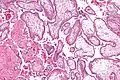

Micrograph showing chorionic villi. Intermediate magnification. H&E stain.

Micrograph showing chorionic villi. Intermediate magnification. H&E stain. Micrograph showing chorionic villi. Very high magnification. H&E stain.